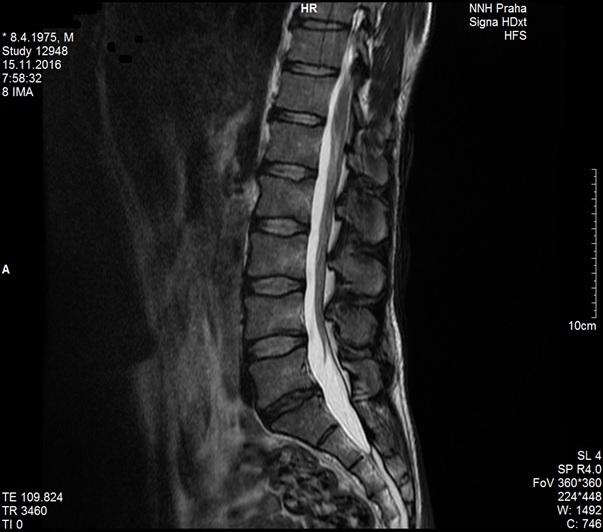

Sekvestr (úlomek) ploténky zmizel po 3 měsících terapie

Na snímku z MR ze dne 24.8.2016 je možné vidět velký sekvestr ploténky

Na snímku ze dne 15.11.2016, tedy po 3 měsících terapie, již není patrný.